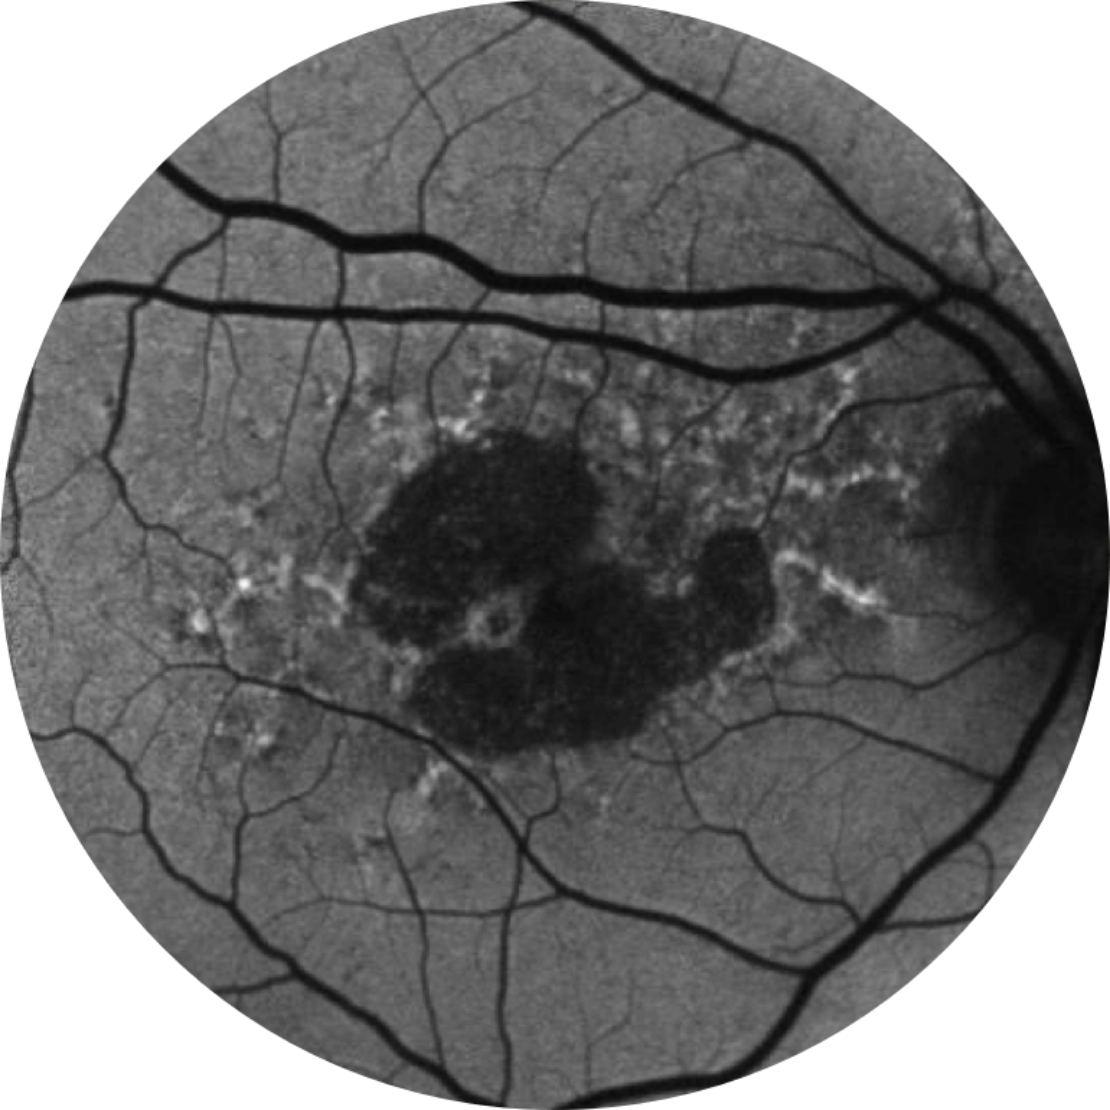

Horizontaler OCT-Scan über der Fovea

Optische Kohärenztomographie (Optical coherence tomography, OCT): Die Atrophie der Netzhautschichten ist mit diesem nicht-invasiven Bildgebungsverfahren deutlich zu erkennen.21